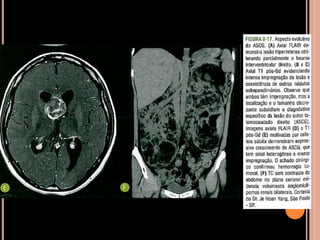

Área de vacuolização de mielina

 Origem é controversa;

 Achado típico em crianças com NF1;

 Focos hiperintensos em T2 e no FLAIR em núcleos

da base, cápsula interna, tronco encefálico e

cerebelo;

 Mais comum no globo pálido, geralmente bilateral;

NF1

Vacuolização de mielina

 Aparecimento geralmente aos 3 anos  aumenta

até os 12 anos  tendência a regredir;

 Raro observar após os 20 anos de idade;